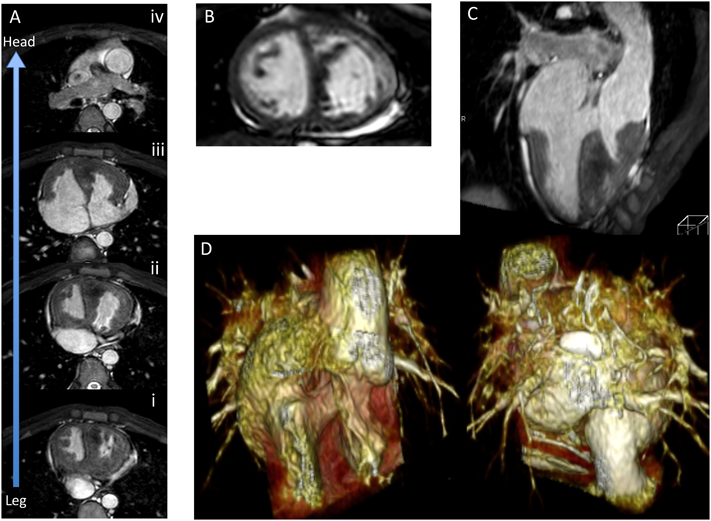

Figs. 16~18に症例を提示する.未手術の修正大血管転位として当院にCMRを依頼された若年成人である.チアノーゼありSpO2は76%,胸骨右縁中部にRevine 4/VIの収縮期駆出性雑音を聴取した.

Pediatric Cardiology and Cardiac Surgery 32(4): 291-306 (2016)

Fig. 15 Cardiac magnetic resonance process of congenital heart disease

まずWHMRAおよびCine MRで全体像を把握する(Fig. 16).Fig. 16AはAxial planeを尾側から頭側に並べたものである.IVCが椎体右を走行し右側心房に還流(心房位正位),右房は右側の心室に接続し,そこから肺動脈が起始している.また左側の心室からは大動脈が起始している.SVCは1本で右房に還流していることが判る.心室は全体的な形態(Fig. 16C, D)や房室弁付着位置,中隔面(Fig. 16B)から右側が左室,左側が右室と判断でき,形態診断としては{S.L.L.} cTGA VSD PS, SVCは1本で無名静脈が存在することがわかる.肺静脈もすべて左側心房に還流しており,VSDは十分に大きい(Fig. 16C, D).Fig. 17A–Cは造影3D MRAであるが,形態情報がより明瞭に得られる.ASDはやや不明瞭ではっきりしないが少なくとも大きな欠損はなさそうである.

Fig. 16 Case presentation: Cardiovascular morphologic assessment {S.L.L.} cTGA PS VSD

A: WHMRA serial axial planes. B: Short axis plane of cine MR. C: Four chamber slab-MIP image. D: Three-dimensional VR image of MRA. cTGA: corrected transposition of great arteries; PS: pulmonary stenosis; VSD: ventricular septum defect; WHMRA: whole heart magnetic resonance angiography.

ついでFlow measurementから得られた各血流量と短軸Cine MRから得られた心室容積を検証し,血行動態を考察する(Fig. 18).得られた血流量を模式図内に矢印とともに記載した.これらの値が正しいかを異なる部位の血流量を比較し検証する.まずMPA 1.5 L/min/m2とRPA 0.7 L/min/m2+LPA 0.7 L/min/m2=1.4 L/min/m2とほぼ一致しており,SVC 0.9 L/min/m2, IVC 1.0 L/min/m2で両者の和1.9 L/min/m2は僧帽弁流入量2.1 L/min/m2とほぼ一致している.また,両心室に流入する全血流量MV 2.1 L/min/m2+TV 2.4 L/min/m2=4.5 L/min/m2は両心室から拍出される全血流量AAo 3.1 L/min/m2+MPA 1.5 L/min/m2=4.6 L/min/m2ともほぼ一致しており,各部位の計測血流量が実際と大きく解離していることはないと確認できる.なお検査時間の短縮のため肺静脈の撮影は施行しなかった.AAoとSVC+IVCの差1.2 L/min/m2は体肺短絡側副血行による肺血流と考えることができ,Qp/Qsは約1.4と算出された.

一方,cine MRからのvolumetryではLV output=2.1 L/min/m2, RV output=2.5 L/min/m2と算出され,それぞれMV flow 2.1 L/min/m2, TV flow 2.4 L/min/m2とほぼ一致しておりvolumetryも真の値と解離していないことが示された.左右心室の拍出量は二心室修復した場合の体循環・肺循環を支えることできるレベルと推測された.なお,房室弁逆流はわずかであった.本症例は造影プロトコールを追加しており,最後に遅延造影を行ったが,基部中隔心筋中層に明らかなLGEを認めた(Fig 17D, E).房室不一致症例は経年的に房室伝導が障害されることがあり,関連性が興味深いところである.

本症例に採択しうる外科治療選択肢として,Conventional Rastelli, Double switch operation(Atrial switch + Rastelli)(DSO),One and a half repair(1+1/2),TCPCが挙げられ,もちろん保存的観察という方針もあり,判断の難しいところだが,少なくとも今回のCMR検査で形態情報に加えて左右心室のポテンシャルが正確に計測されたことで,心室機能がDSOや1+1/2手術を断念する理由にはならない一つの根拠になると考えられた.

Fig. 17 Contrast-enhanced three-dimensional magnetic resonance angiography and late gadolinium enhancement

A: VSD. B: Pulmonary vein, normal return. C: Pulmonary stenosis. D,E: Late gadolinium enhancement.